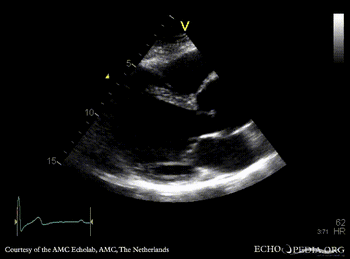

M-Mode through aortic root PLAX with Color Doppler: moderate aortic regurgitation